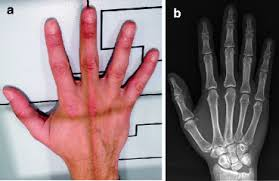

in regards to the 2nd-5th digits, what are the 3 Phalanges (3)? (name them and picture where they go)

Distal, Middle, Proximal

in regards to the 2nd-5th digits, what are their Joints(2)? (name them and picture where they go)

Distal Interphalangeal Joint, Proximal Interphalangeal Joint

in regards to the 1st digits, what are their Phalanges (2)? (name them and picture where they go)

Distal, Proximal

Largest Carpal Bone is what bone?

Capitate

Smallest Carpal Bone is what bone?

Pisiform